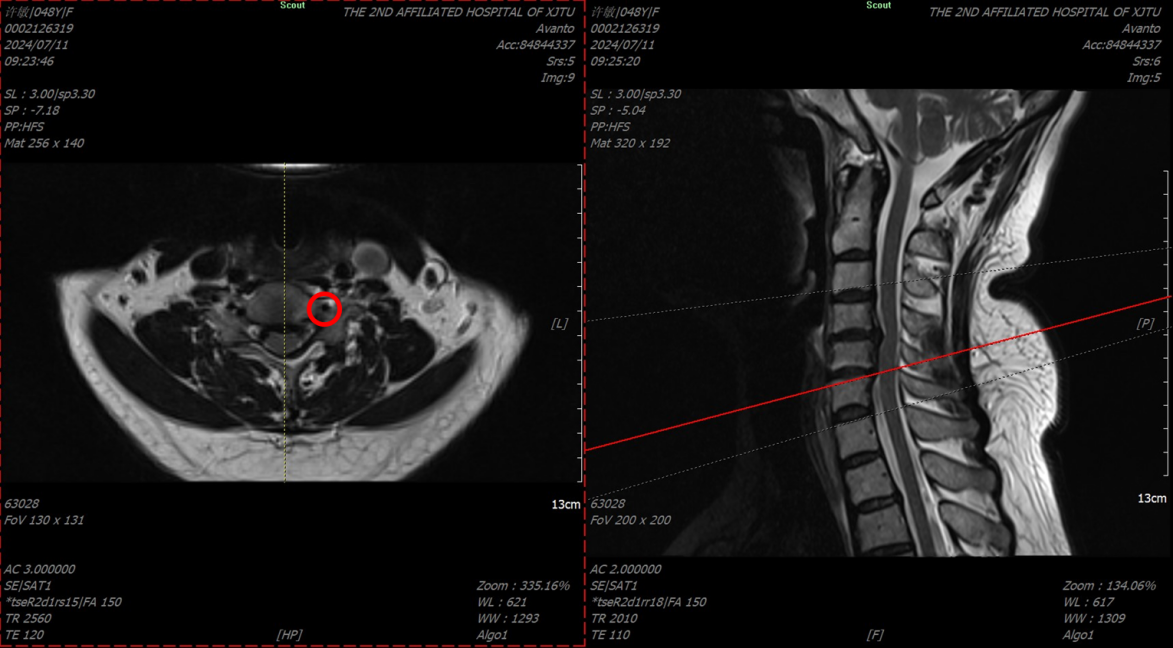

图3颈椎MRI(椎动脉在颈5/6层面存在受压)

来自陕西省渭南市的许某被头晕症状折磨了8年之久,犯病时伴有濒死感、心慌、胸闷、气短、大汗,偶尔伴有耳鸣及听力减退等症状,十分痛苦。反复就诊于不同级别的医院,要么被误诊为颅内疾病、冠心病、或高血压等疾病,结果治疗无效;要么确诊为颈椎病,但因未接受手术治疗,导致症状反复无法缓解。1月前患者怀着忐忑的心情就诊于我院神经内科,展淑琴主任团队快速给患者完善了颅脑MR 3T平扫、头颅MR血管成像、颈部MR增强血管扫描等专科检查,均未见明显异常(图1),考虑该患者头晕可能与颅内疾病关系不大,于是联系耳鼻喉科、骨科中心骨病与创伤病区等多学科会诊。张纯主任通过详细询问病史、认真查体后初步考虑该患者头晕可能系颈椎病所致,并嘱患者完善颈椎MRI及颈椎正侧双斜位片检查进一步确认。经过仔细查阅加拍的影像学检查,张纯主任发现,患者颈4/5、颈5/6椎间盘突出严重,相应椎管狭窄;最为重要的是颈椎双斜位片上左侧颈5/6钩椎关节增生明显(图2),且从MRI轴位片上可以看到椎动脉在颈5/6层面存在受压(图3),于是向患者告知病情,并果断建议其手术治疗。患者饱受头晕困扰,鉴于张纯主任每次交流中均展现出的专业素养和工作态度,患者毫不犹豫地选择手术治疗,遂转入骨科中心骨病与创伤病区。经过骨三科护理团队专业的术前准备和医生团队详细的术前规划,在麻醉团队、手术护理团队的保驾护航下,张纯主任主刀,高宗强主任医师及李永伟博士协助,为患者实施了颈椎前路椎管减压术,术中张纯主任仔细操作,反复检查椎动脉减压效果,直至减压满意。术后3天给与患者复查术后X线片,显示非常满意(图4)。患者下地活动后发现头晕症状完全缓解,出院后1周还特地与张纯主任取得联系,告知“现在一点都不晕了”。医生的专业判断、果断决策及精准手术,加之患者的高度配合,使得手术得以顺利、成功进行。